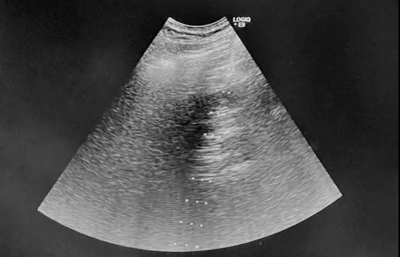

各相关科室专家经过MDT小组讨论,为这例肝癌患者制定了个体化方案。先局麻下超声引导经皮肝脏肿瘤射频消融治疗控制肿瘤进展,再适时行冠脉支架治疗,冠心病改善后再择期行腹腔镜胆囊切除术。肝癌射频消融治疗于局麻下实施,将心血管风险降至最低,又能很好的控制肿瘤,对于3cm大小肝癌甚至达到手术切除效果。患者及家属心情非常激动,消除了顾虑,安心等待治疗。

1月17日,陈涛主任下班后,时间已经很晚了,本想跟患者及家属协商更改手术时间,但为了患者安危,为了家属安心,陈主任毅然从新街口院区赶往回龙观院区。经过充分准备,晚7点多手术开始。超声科陈涛主任熟练地操控超声探头进行引导,由普外科毕敬涛主任负责穿刺,普外科孔娜主治医师和荀晓冬住院医师配合,最终顺利完成经皮肝肿瘤射频消融术。患者痛苦很小,操作过程顺利,患者及家属万分感激。